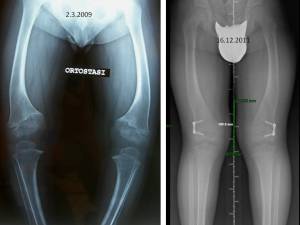

Si tratta di pazienti portati a consultazione in genere fra i 6 e i 12 anni, che presentano un difetto di torsione degli arti inferiori quasi sempre associato ad esagerata antiversione del collo femorale. Quando vengono osservati di fronte, con il bordo interno dei piedi accostato, le rotule guardano all’interno – “strabismo rotuleo convergente”, le ginocchia sembrano vare e la testa del perone sporge più del normale. Se il bambino viene posto con le rotule frontali, le punte dei piedi divergono ed il varismo, se apparente svanirà del tutto, o si attenuerà solo in parte (fig 4). In questi casi, per una corretta valutazione, è opportuno eseguire delle radiografie panoramiche degli arti inferiori in ortostasi, sia con i piedi accostati (rotule convergenti) sia con i piedi extra ruotati di circa 30° (rotule frontali), in modo da misurare l’asse meccanico e poter capire se vi sono indicazioni chirurgiche.

La componente di varismo, se presente, in questo caso si parla di varismo idiopatico (fig 5 AB), può essere ridotta con interventi di modulazione della crescita mediante applicazione di 8-plates sul versante esterno della cartilagine di accrescimento della tibia prossimale (fig 5 CD-EF).

Fig. 5: anni 11 e 8/12, tibia vara costituzionale con componente torsionale. DIC: 6 cm con rotule allo zenith (A), DIC: 5 cm con piedi extra ruotati di 30° (B); in pratica il varismo persiste anche con gli arti in extrarotazione. C) Quadro radiografico. D) La componente di varismo può essere migliorata con interventi di modulazione della crescita, mediante applicazione di piccole placche a forma di “8” in corrispondenza della parte laterale della cartilagine di accrescimento della tibia prossimale. E-F) In quest’immagine è possibile confrontare l’aspetto della ginocchia prima dell’operazione (E) e dopo 2 anni dall’intervento chirurgico di epifisiodesi asimmetrica tibiale esterna (F). L’asse meccanico delle ginocchia è migliorato, persiste invariata l’alterazione torsionale.